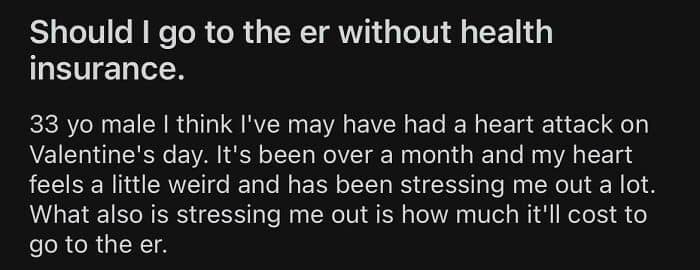

#30 When You Live In America And Can’t Afford Healthcare

#55 The American Healthcare System, Not Rich Enough To Live